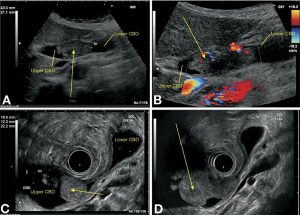

سونوگرافی (Ultrasound)

اولتراسوند از امواج صوتی و پژواک آنها برای ایجاد تصاویری از داخل بدن استفاده میکند. ابزار کوچکی به نام مبدل، امواج صوتی را منتشر میکند و پژواکها را در حین بازگشت از اندامهای داخل بدن دریافت میکند. پژواکها توسط کامپیوتر به تصویر روی صفحه تبدیل میشوند.

سونوگرافی شکمی (Abdominal ultrasound): این اغلب اولین آزمایش تصویر برداری است که در افرادی که علائمی مانند زردی یا درد در سمت راست بالای شکم دارند، انجام میشود. این کار یک آزمایش آسان بوده و از تشعشع استفاده نمیکند. شما به سادگی روی یک میز دراز میکشید در حالی که یک تکنسین مبدل را روی پوست روی شکم شما حرکت میدهد.

این نوع سونوگرافی همچنین میتواند برای هدایت سوزن به ناحیه یا غدد لنفاوی مشکوک استفاده شود تا بتوان سلولها را برداشت (بیوپسی) کرده و زیر میکروسکوپ مشاهده کرد. این روش بیوپسی سوزنی با هدایت اولتراسوند (ultrasound-guided needle biopsy) نامیده میشود.

سونوگرافی آندوسکوپی (Endoscopic) یا لاپاراسکوپی (laparoscopic): در این تکنیکها، پزشک مبدل اولتراسوند را در داخل بدن شما و نزدیکتر به مجرای صفراوی قرار میدهد. این روش تصاویر را با جزئیات بیشتری نسبت به سونوگرافی استاندارد ارائه میدهد.

مبدل در انتهای یک لوله نازک و روشن قرار دارد که یک دوربین روی آن قرار دارد. این لوله یا از طریق دهان، از طریق معده به پایین و به روده کوچک در نزدیکی مجاری صفراوی (سونوگرافی آندوسکوپی) یا از طریق یک برش جراحی کوچک در پوست بدن شما (سونوگرافی لاپاراسکوپی) به بدن وارد میشود.

اگر تومور وجود داشته باشد، پزشک ممکن است بتواند میزان رشد و گسترش آن را ببیند که همین امر میتواند به برنامه ریزی برای جراحی کمک کند.

سونوگرافی ممکن است بتواند بزرگ شدن غدد لنفاوی مجاور را نشان دهد که میتواند نشانه ای از رسیدن سرطان به آنها باشد. بیوپسی سوزنی (Needle biopsy) از نواحی مشکوک نیز ممکن است انجام شود.